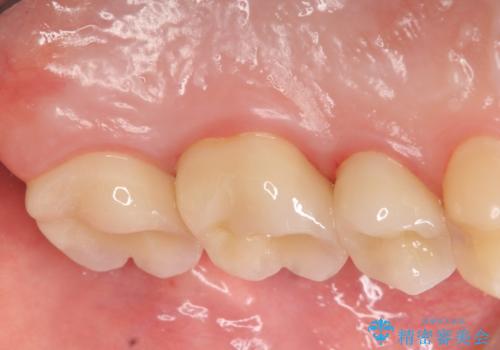

オールセラミッククラウン 痛みでものが咬めない歯の治療

- 左上の歯が痛くてものが咬めないといらっしゃった方の症例です。

左上6は自発痛および持続痛を認めたため根管治療後、オールセラミッククラウンによる補綴を行いました。

左上7は冷水痛のみだったため、慎重に虫歯の除去を行い症状がないことを確認後、オールセラミッククラウンによる補綴を行いました。

左上5は再根管治療後、オールセラミッククラウンによる補綴を行いました。

今回用いたオールセラミッククラウンはジルコニアフレームという白い素材の上にセラミックを盛っているため、審美性が非常に高いのが特徴です。

また、ジルコニアは人工ダイヤモンドの材料にも使われているほど高い強度を持っており、そのためオールセラミッククラウンは審美性だけでなく、奥歯やブリッジの補綴も可能とするクラウンです。